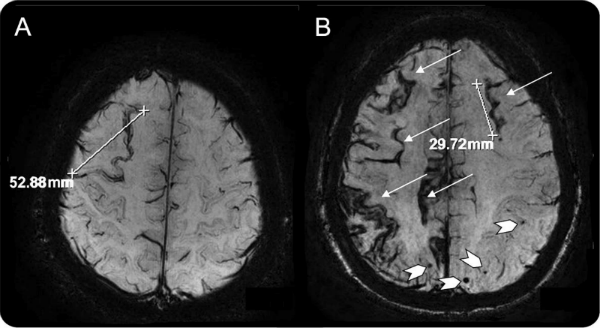

Imagem 2

Imagem 2: A imagem demonstra um padrão radiológico clássico de angiopatia amiloide cerebral, caracterizado por hemorragia lobar, micro-hemorragias corticais múltiplas e siderose cortical superficial, preenchendo critérios para AAC provável e com implicações terapêuticas críticas, sobretudo no que diz respeito à evitação de terapias antitrombóticas.

Fonte: https://www.alzforum.org/news/research-news/alzheimers-disease-linked-superficial-siderosis-what-does-it-mean